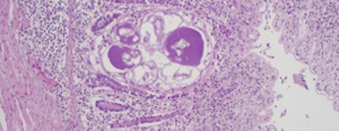

Veulen verworpen op 9 maanden dracht, infectieuze oorzaken uitsluiten.

Lees verder